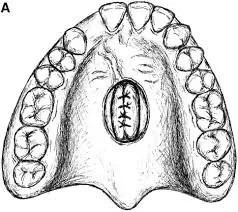

Reparació de Fístules oronasals

Una fístula és una comunicació anòmala entre dos òrgans que pot ser d'origen congènit o secundari a múltiples causes. Les fístules oronasals són la comunicació anormal entre la boca i el nas, i es tracta de la complicació més freqüent de la cirurgia de la fissura palatina.

En quin percentatge de casos passa?

La incidència és molt variable en funció de la dificultat del tancament primari de paladar i en funció de l'experiència del cirurgià. En les sèries estan descrites incidències des del 4 al 35%, sent més freqüents en les fissures palatines bilaterals.

Quins símptomes produeixen?

Fonamentalment es diagnostiquen per la sortida de líquid o aliment a través del nas i per les dificultats en la pronunciació (hipernasalitat).

Quin és el tractament?

Segons la localització i la mida s'han descrit multitud de tècniques. Les més habituals són penjolls locals, bé del mateix paladar, de la mucosa oral o lingual. També s'han descrit l'ús de penjalls lliures (procedents de zones més allunyades del cos) o l'ús de materials sintètics. La recidiva (reproducció) de la fístula es calcula que és d'aproximadament un 25%.